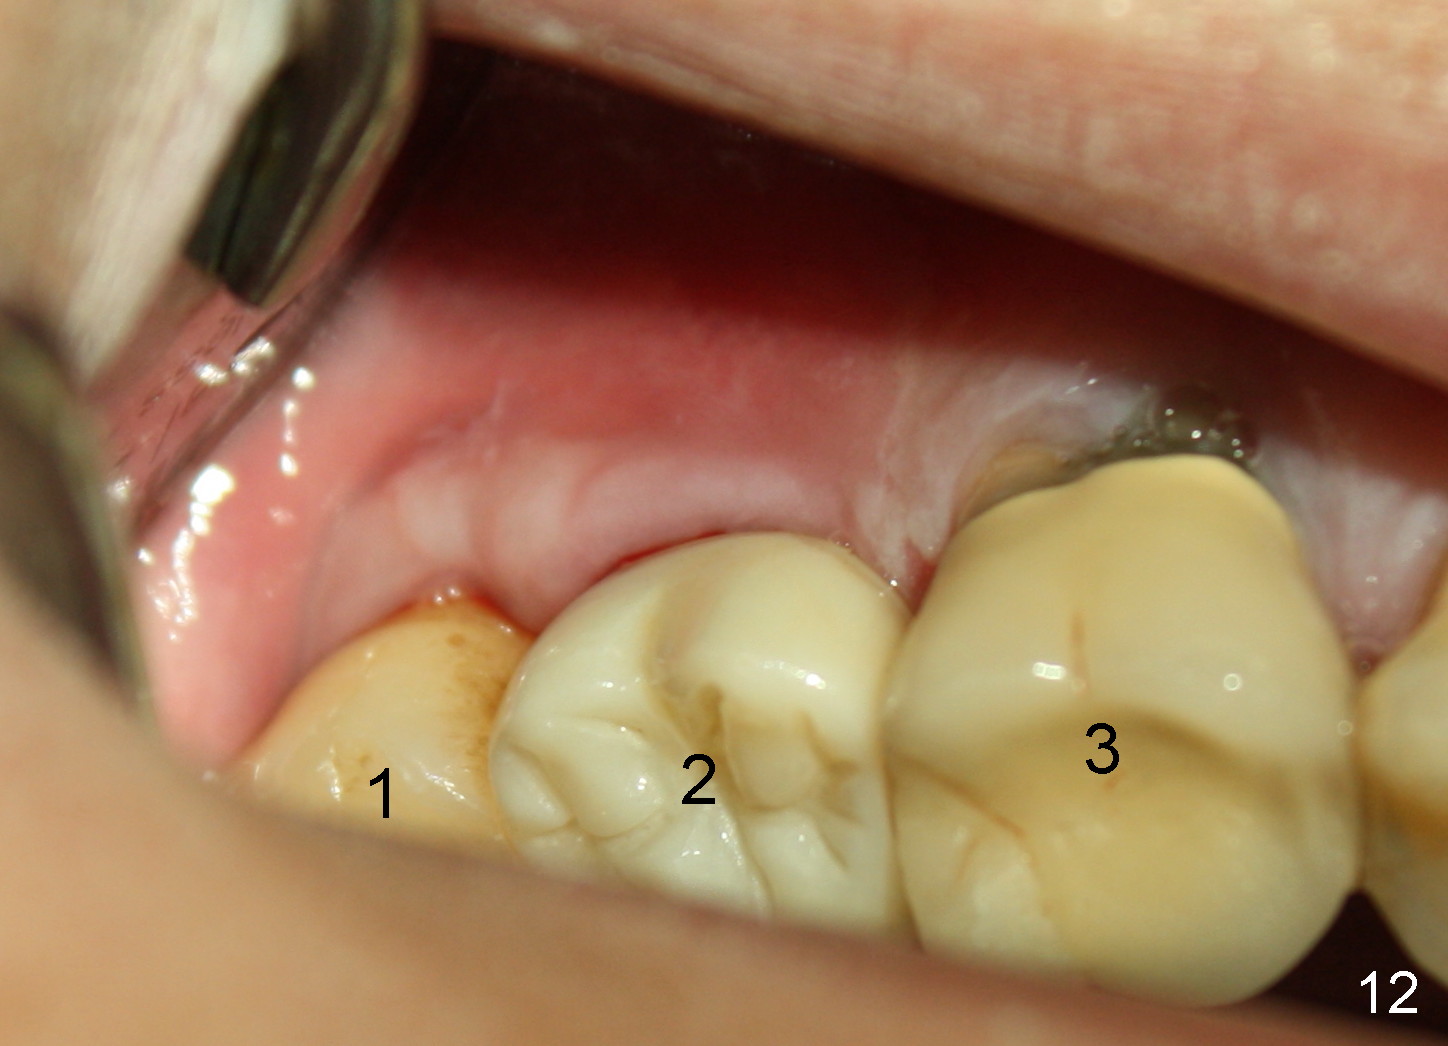

The patient complains food impaction between #1 and 2, six months post cementation. The former has mobility II. Although there is keratinized gingiva buccal to these sites (Fig.12), there is no papilla buccally (Fig.13) or palatally (Fig.14). The palatal pockets between #1 and 2 are deep with tenderness. X-ray shows bone loss between the sites (Fig.11 white *); the periodontal explorer can be felt to touch the distal implant threads (<). Extraction and immediate implant are recommended for #1. Twelve months later, the patient agrees with the treatment plan. The tooth #3 needs extraction and immediate implant, 2.5 years after the one at #2.